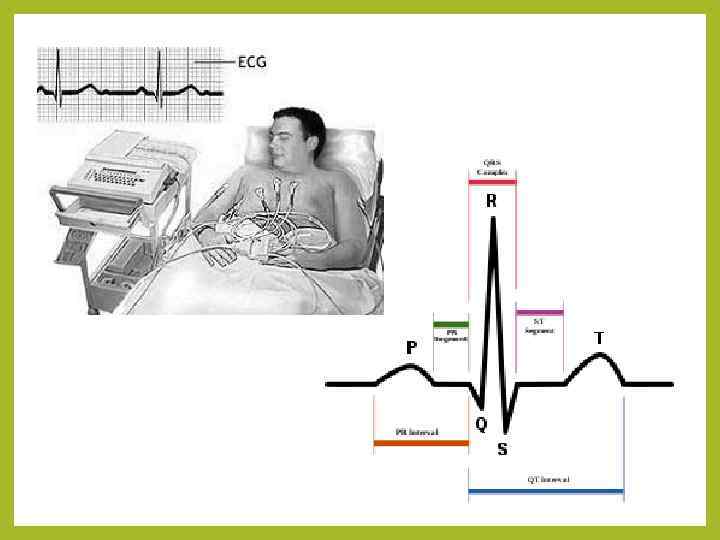

ЭКГ